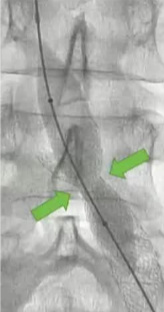

![]() if you look hard enough,如果你的眼睛睁的足够大,你就不难发现,通常下肢血栓清除后是潜在的静脉狭窄 术前的影像检查能为您提供一些线索:可能存在动脉受压的情况;或者淋巴结或其他肿块压迫了静脉。 血栓的上限通常标志着狭窄的部位。 术中血管内超声检查是最准确的。

其它考虑怎么做?How to do IT? 1. 建议将静脉段的扩张程度控制在与所选支架直径相匹配的范围内。【Rahmani 2023 Gibson 2022 Cirse SOP 2014 Raju 2013】 狭窄血管的过度扩张通常不会导致破裂,即便在慢性闭塞的情况下,血管也能承受较大的球囊扩张,并在随后置入较大的支架而不会发生破裂。 只有在以下情况才需例外处理:即在腹膜后区域或鞘管 环绕外科手术已经打开的静脉【joyce DP 2024】 对于慢性静脉阻塞的情况,采用逐渐增大直径的球囊进行多次扩张操作可能并非必要。 除非您无法将 14/16 毫米的气囊顺利穿过病变部位,否则可能需要进行多次扩张操作。【Barbati 2014】 2. 此外,该操作应贯穿整个病变部位的整个长度进行。【Oropailo 2023 Lichtenberg 2018】 ![]() 3. 使用高压球囊【Oropallo A 2023 Gibson 2022】 44岁 男 2次左髂股静脉血栓形成,以下静脉造影